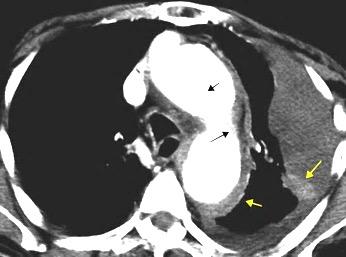

Signo de la Pleura separada “Split pleural sign”

Capas pleurales de grosor uniforme realzadas por el contraste

No específico de empiema. Indica “exudado”. 68% de pacientes con empiema pleural.

Capas pleurales de grosor uniforme

Realce grasa extrapleural (30%)

> Grasa Extrapleural. (60-80%)

Kraus GJ. Split pleural sign. Radiology 2007

Pleural visceral 50%

Pleural parietal 100%